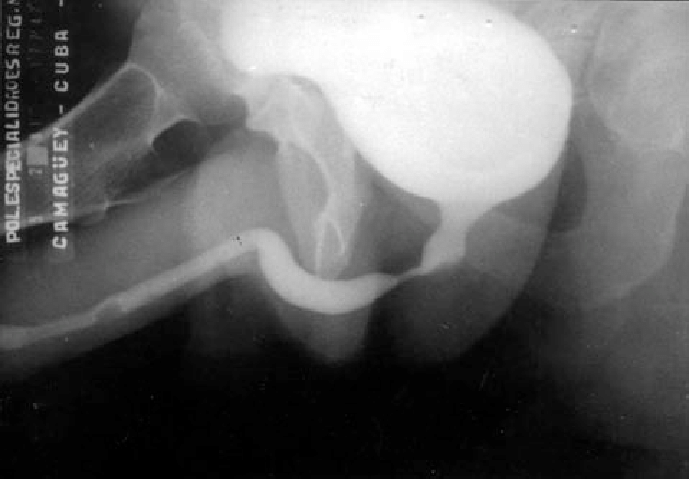

RADIOGRAFIA SIMPLE

Como apoyo diagnostico para patologia uretral, estenosis uretra. No como examen de tamizaje Sindrome de tracto inferior mas estos antecedentes (ITS, intrumentalizacion, traumas de uretra),  se sospecha lesion estenotica de la uretra. Se puede evaluar la distancia de la lesion estenotica, nivel de inicio y termino. A diferencia de la cistoscopia en el que con una camra con fuente de luz se entra por la uretra llegando a la vejiga. Muy invasivo. Radiografia simple con contraste: Se aplica medio de contraste en la vejiga, por puncion o con sonda, pudiendo evaluar el trauma, uropatia obstructiva bja, o zona que no este distendiendose adecuadamente, rotura, lesion de vejiga. No sirve para ver litiasis, es poco sensible pero muy especifica. Existen piedras radioopacas y radiolucidas

La radiografia entiempo real sirve para apoyo en procedimiento quirirgicos y diagnsoticos. Litiotripsia extracorporea: Un calculo ubicado en la zona del ureter proximal o riñon, que mida <2 cm y que sea radiopoca se puede fragmentar mediante ondas de choque. Para esto se utlizan radiografias en tiempo real. Uretrocistografia (vejiga mas uretra): Tambien se utiliza la radiografia cuando ya se inyecto el contraste.